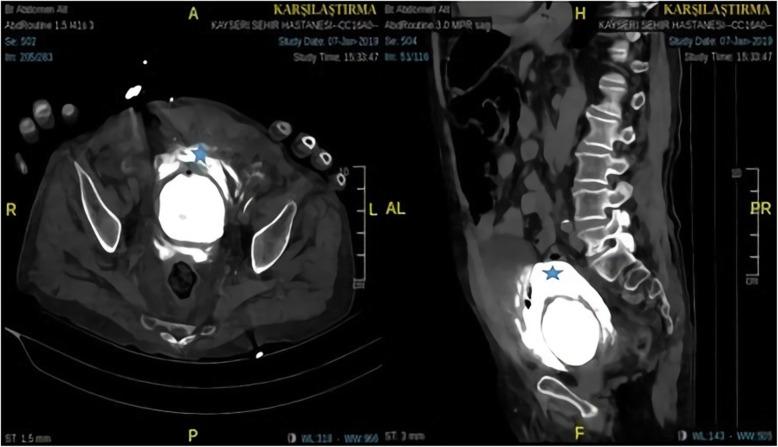

A 77-year-old Caucasian male patient was admitted to the emergency department with abdominal pain, haematuria, and a reduced volume of urine lasting for three days. The patient's amount of urine was reduced, and he came to the hospital for the first time with this complaint. The patient had local bruises on his arms and legs. From the ultrasound, retrograde cystography and computed tomography images, it was thought that there was blood accumulation due to bladder rupture to the intraperitoneal region. Spontaneous bladder rupture secondary to warfarin overdose was considered for this patient who also had an international normalized ratio (INR) level of 13.4. After the INR level was normalized with vitamin K and a prothrombin complex concentrate, the patient underwent surgery. During the operation, a catheter was placed in the bladder, and the bladder mucosa and muscle were closed separately with a primary repair performed by a urologist. The patient was discharged on the 8th postoperative day without any complications.

一名 77 岁的白人男性患者因腹痛、血尿和少尿 3 天入院到急诊科。患者的尿量减少,他第一次因这种症状来医院就诊。患者的手臂和腿部有局部瘀伤。从超声、逆行膀胱造影和计算机断层扫描图像来看,考虑到有血液积聚导致膀胱破裂到腹腔区域。考虑到患者的国际标准化比值(INR)水平为 13.4,因此认为该患者为华法林过量导致的自发性膀胱破裂。INR 水平用维生素 K 和凝血酶原复合物浓缩物正常化后,患者接受了手术。手术中,在膀胱内放置了一根导管,泌尿科医生分别对膀胱黏膜和肌肉进行了一期修复。患者在术后第 8 天没有任何并发症出院。